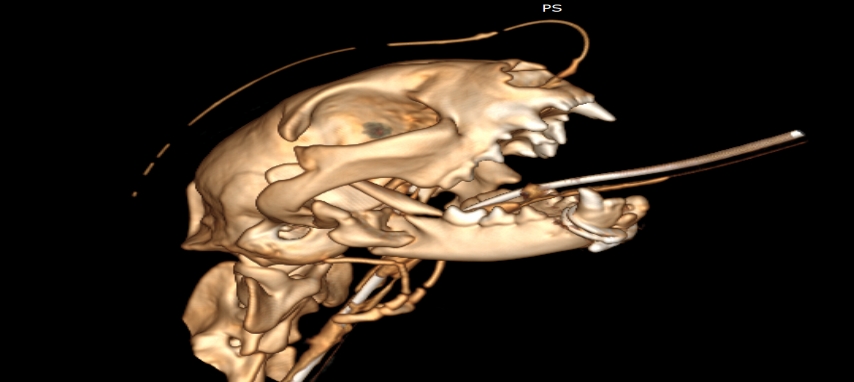

狗狗電腦斷層掃描 不明原因口腔出血 嚴重牙周病 口腔惡性腫瘤 鱗狀上皮細胞癌(Squamous cell carcinoma,SCC)

主訴嘴巴突然流血 口腔潰爛 左下顎腫脹 同時有嚴重牙周病 經由口腔採樣 電腦斷層掃描 確認為鱗狀上皮細胞癌(Squamous cell carcinoma,SCC)同時已經侵犯下顎骨。確診後經由外科醫師、腫瘤科醫師、電腦斷層影像科醫師共同擬定治療計畫後

,大範圍切除左下顎,經過一年追蹤,目前狗狗一切安好喔。

*電腦斷層影像

貓咪 下顎骨骨折

頭骨結構較為複雜 頭骨骨折相對於四肢長骨骨折 不容易靠xray 完整評估術前需要靠電腦斷層影像檢查評估骨折狀況才能良好評估手術方式 提高成功率